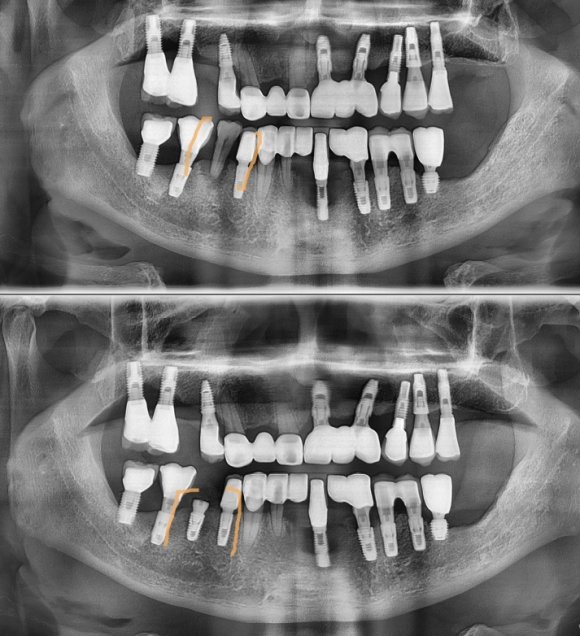

발치 후 뼈이식과 기다림 없이 즉시 식립을 한 임플란트 <주황색 부위>

P.S. 다른부위 임플란트는 옛날에 다른 치과에서..... 할말하..